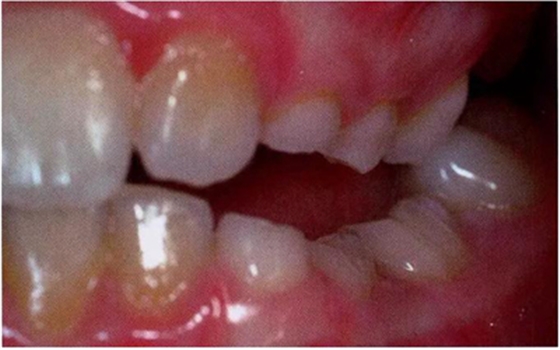

臨床檢查看到合平面出現(xiàn)擾動(dòng)可做為診斷依據(jù)。下沉乳磨牙位于合平面的凸起端(圖4)。這些牙齒在使用金屬器具敲擊時(shí),會(huì)發(fā)出典型的高調(diào),固連“有裂紋茶杯”聲。同時(shí)還需要做影像學(xué)檢查,以確認(rèn)繼承恒磨牙是否缺失。

圖4:由于乳牙下沉而導(dǎo)致合平面發(fā)生改變的臨床像